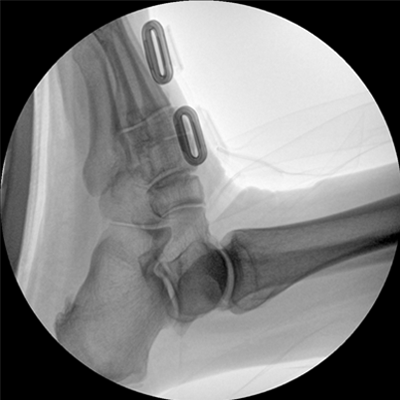

Clinical picture

臨床圖片